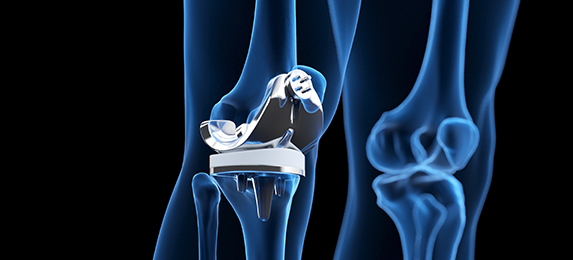

무릎·고관절 통증으로 줄어든 활동을, 다시 편안하게

퇴행성 관절염 등으로 통증과 변형이 심한 경우, 상태에 맞춰 치료 방법을 안내합니다.

어깨 통증·파열로 일상 동작이 어려운 경우부터, 관절염으로 통증과 기능 저하가 큰 경우까지 상태에 맞춘 치료를 안내합니다. 보존적 치료(약물·주사·물리치료)부터 관절경 수술, 필요 시 무릎·고관절·어깨 인공관절 전치환술까지 단계적으로 상담합니다.

통증·기능 저하가 큰 어깨에 인공관절을 삽입해 회복을 돕습니다.